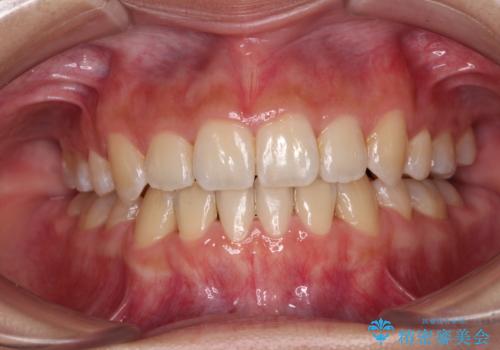

下の歯のがたつき 上より気になる

口元大事です! 見違える矯正!! 乱ぐい歯もあきらめないでください。